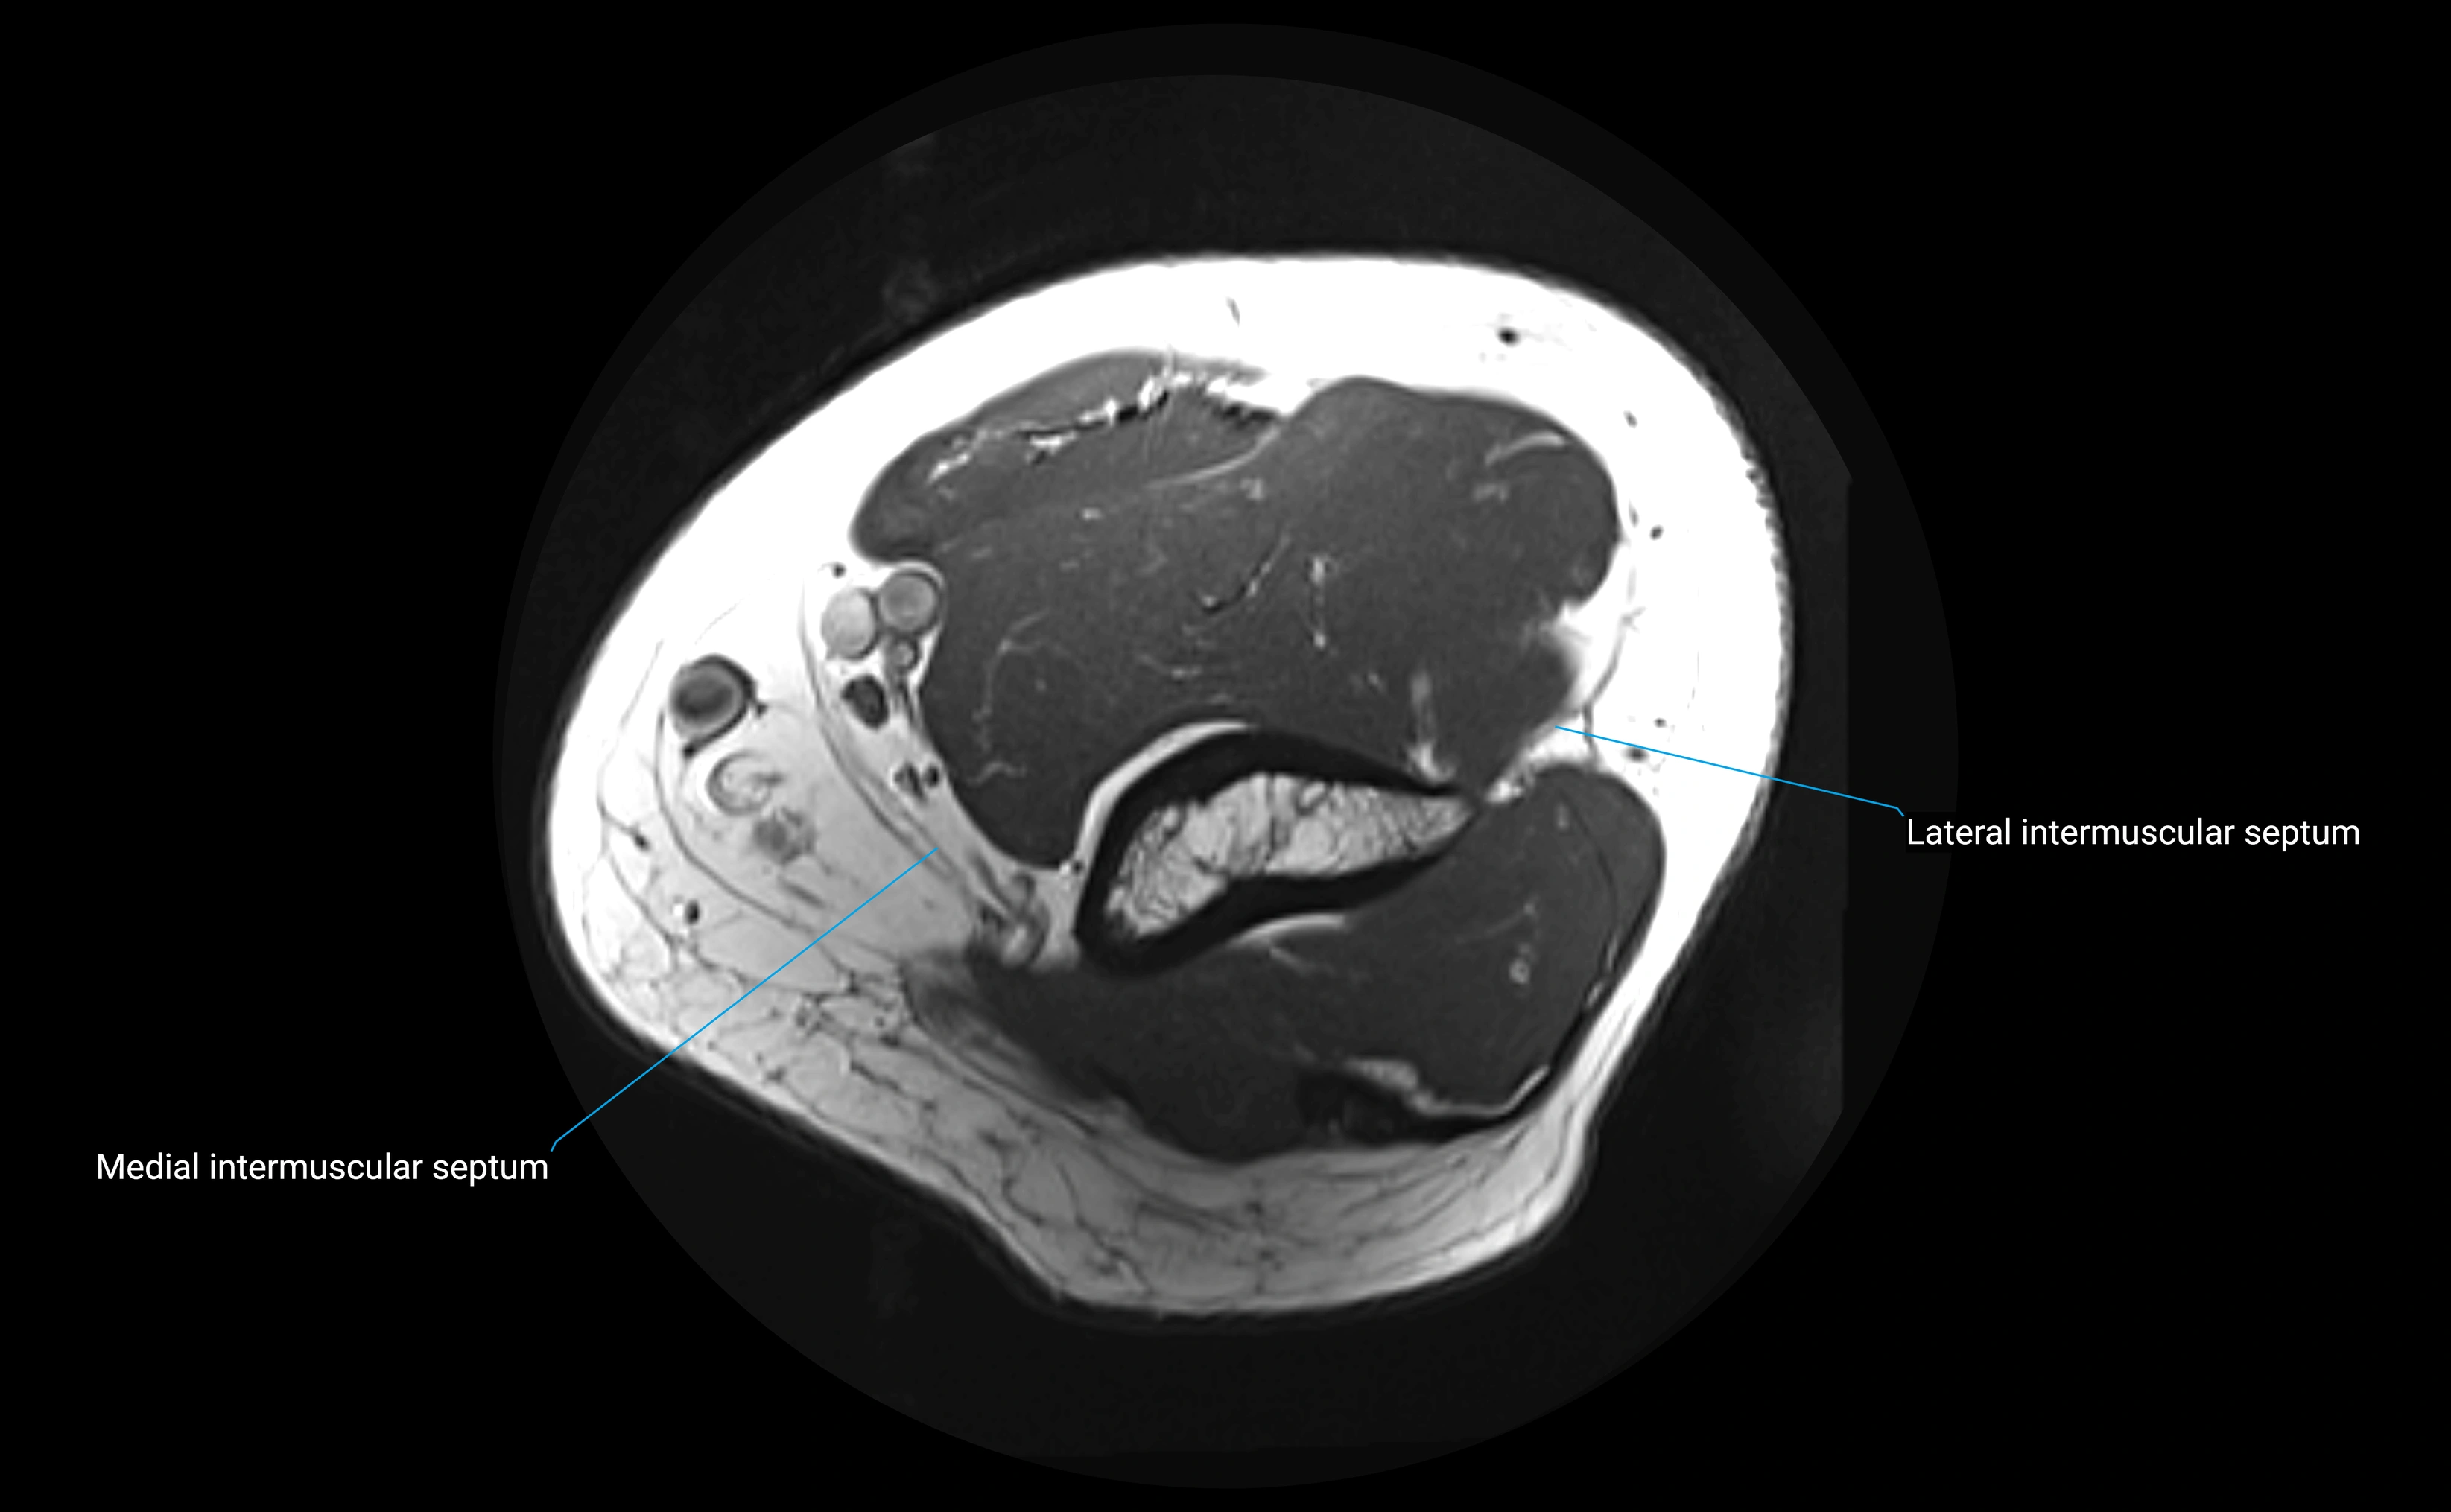

MRI images

image